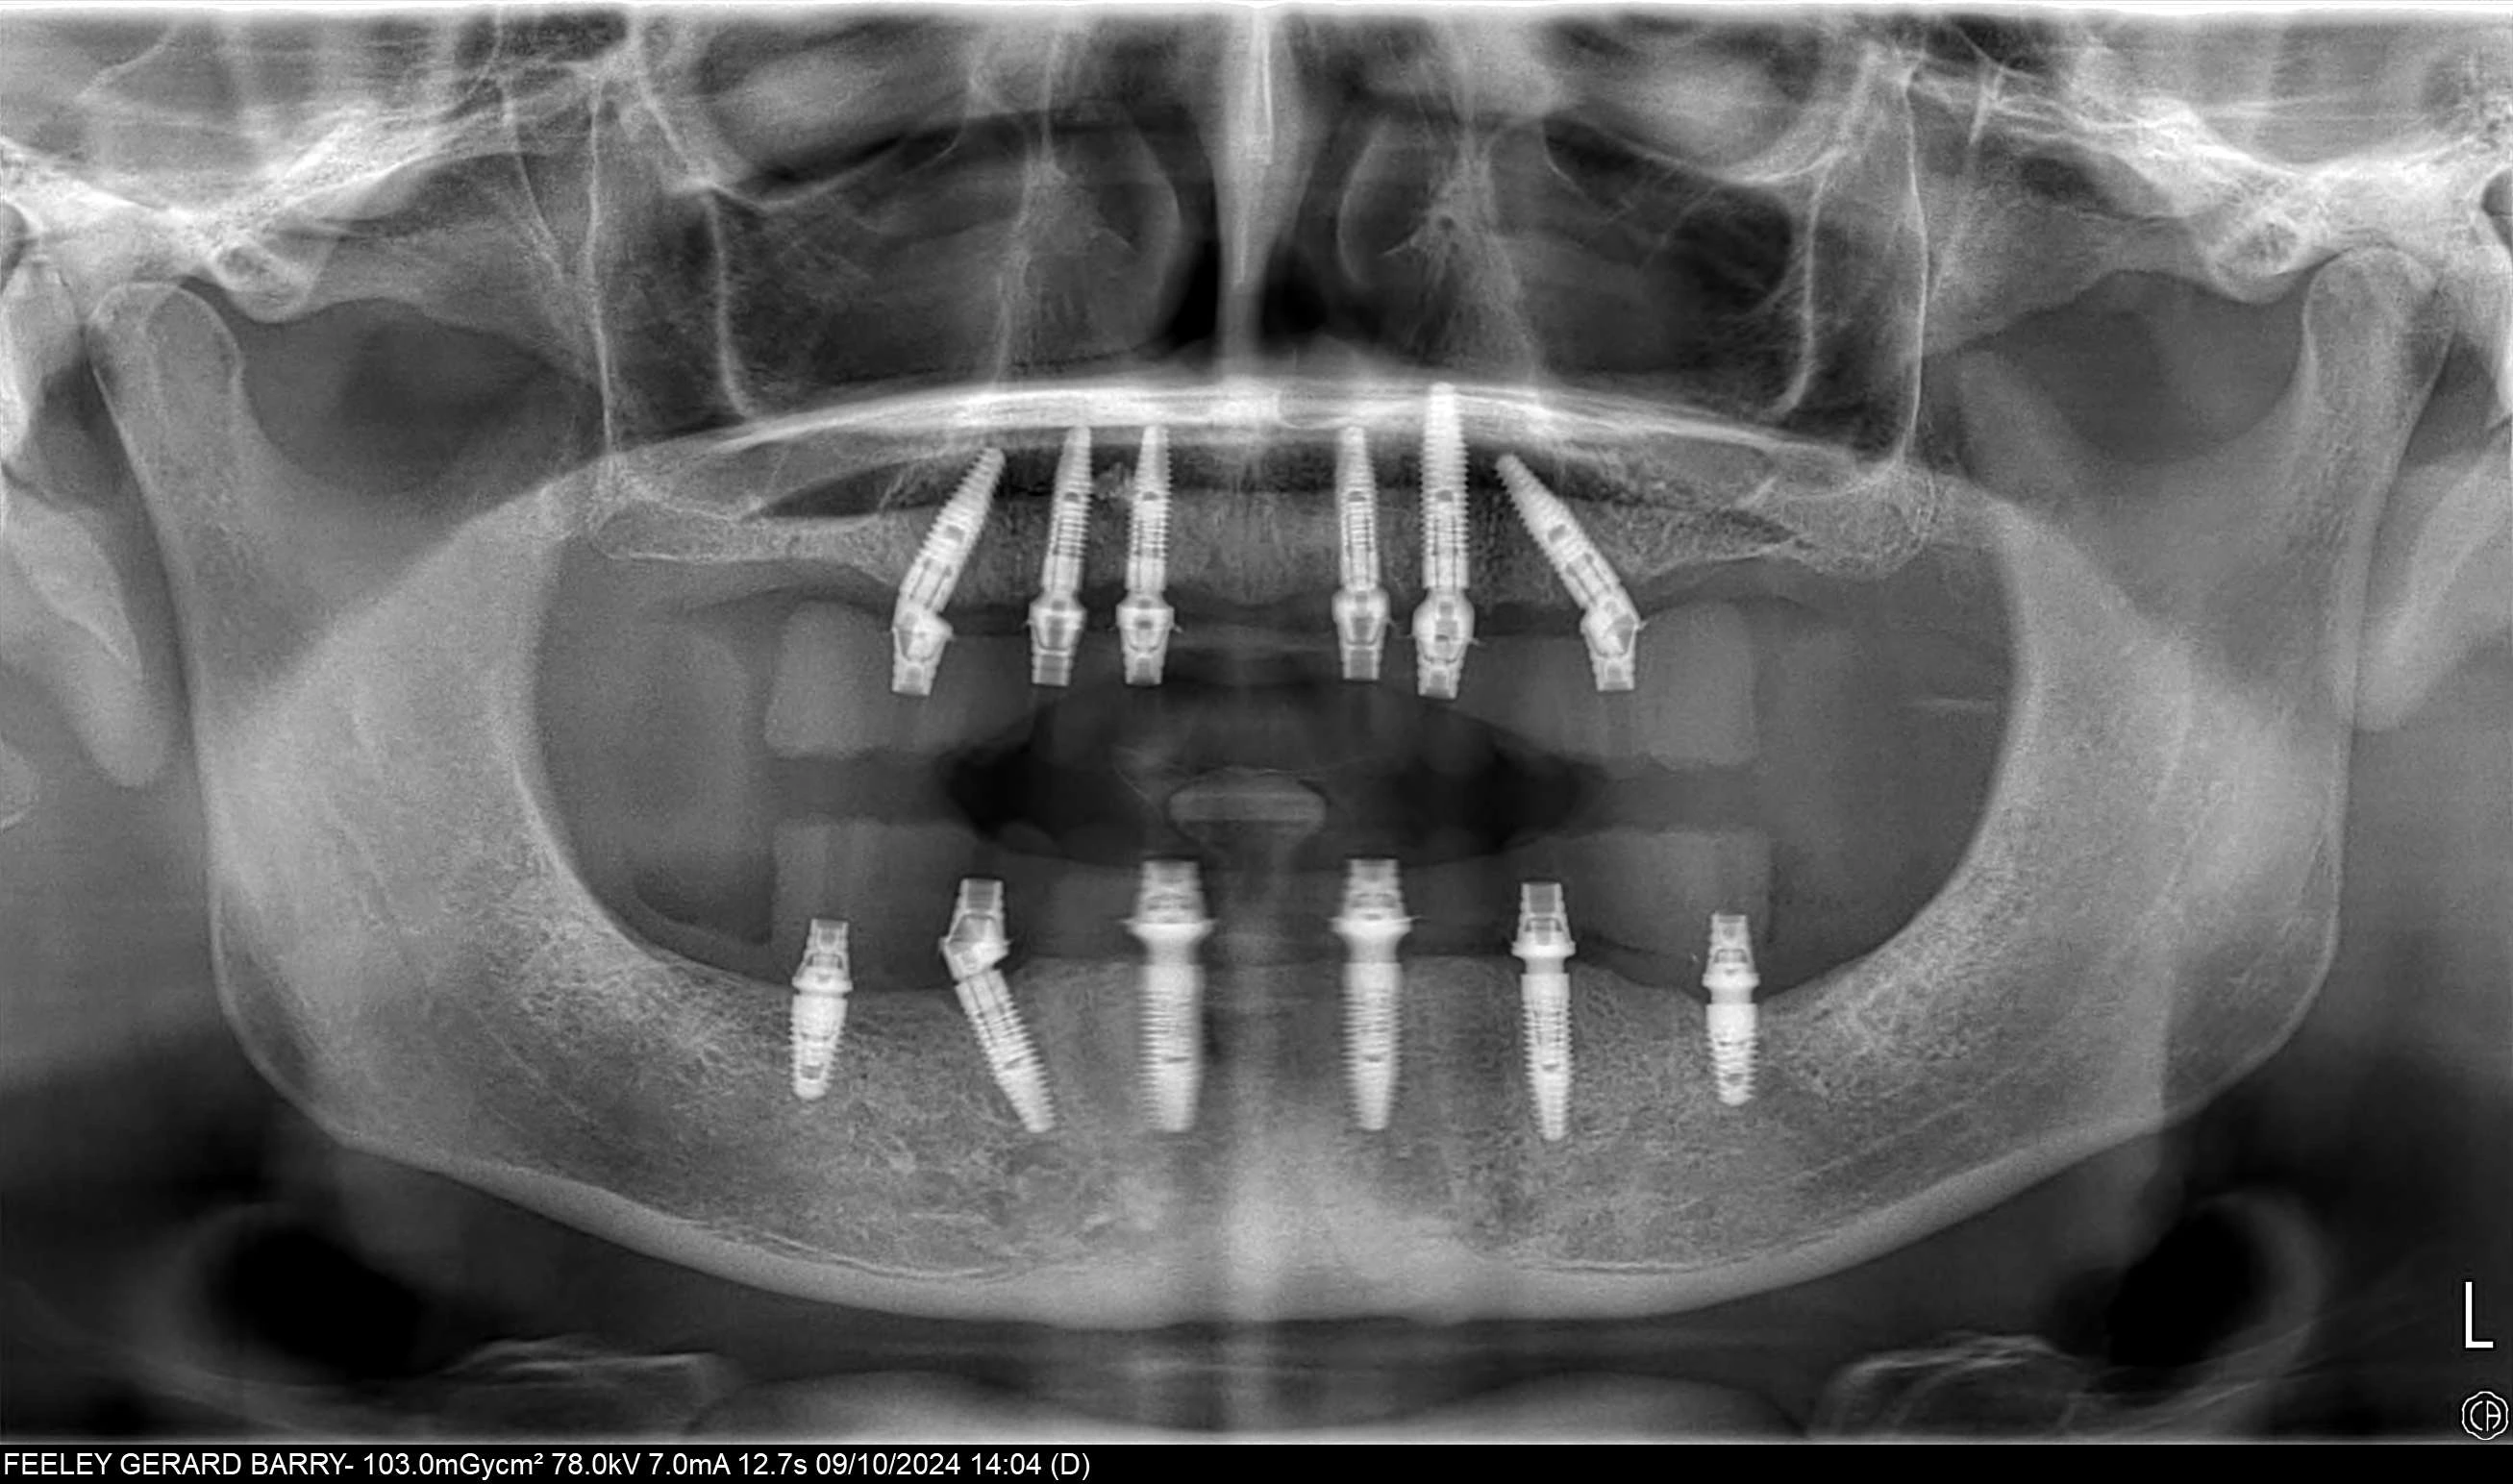

At Attelia, our All-on-6 restorations are supported by a titanium frame that provides superior durability and ensures chewing forces are distributed equally across all six implants. This enhances patient comfort and guarantees long-term success. To increase precision and functionality, we use multi-unit abutments on each implant, ensuring optimum angles, alignment, and a more natural bite.

This advanced approach—which requires high-level expertise, meticulous planning, and extensive clinical experience—not only improves overall stability and comfort but also provides a significant advantage for patients with mild to moderate bone loss. It allows for correct prosthetic positioning even when implants are placed at different angles.

Tooth loss affects more than just your ability to chew; it can impact your speech, self-confidence, and overall facial appearance. All-on-6 dental implants offer a modern, full-arch restoration for patients with multiple missing teeth, providing a stable, comfortable, and permanent solution. In this technique, six biocompatible titanium implants are strategically placed in the jawbone to support full-arch prosthetic teeth. These implants act as a powerful anchor, creating a secure foundation for your new smile.